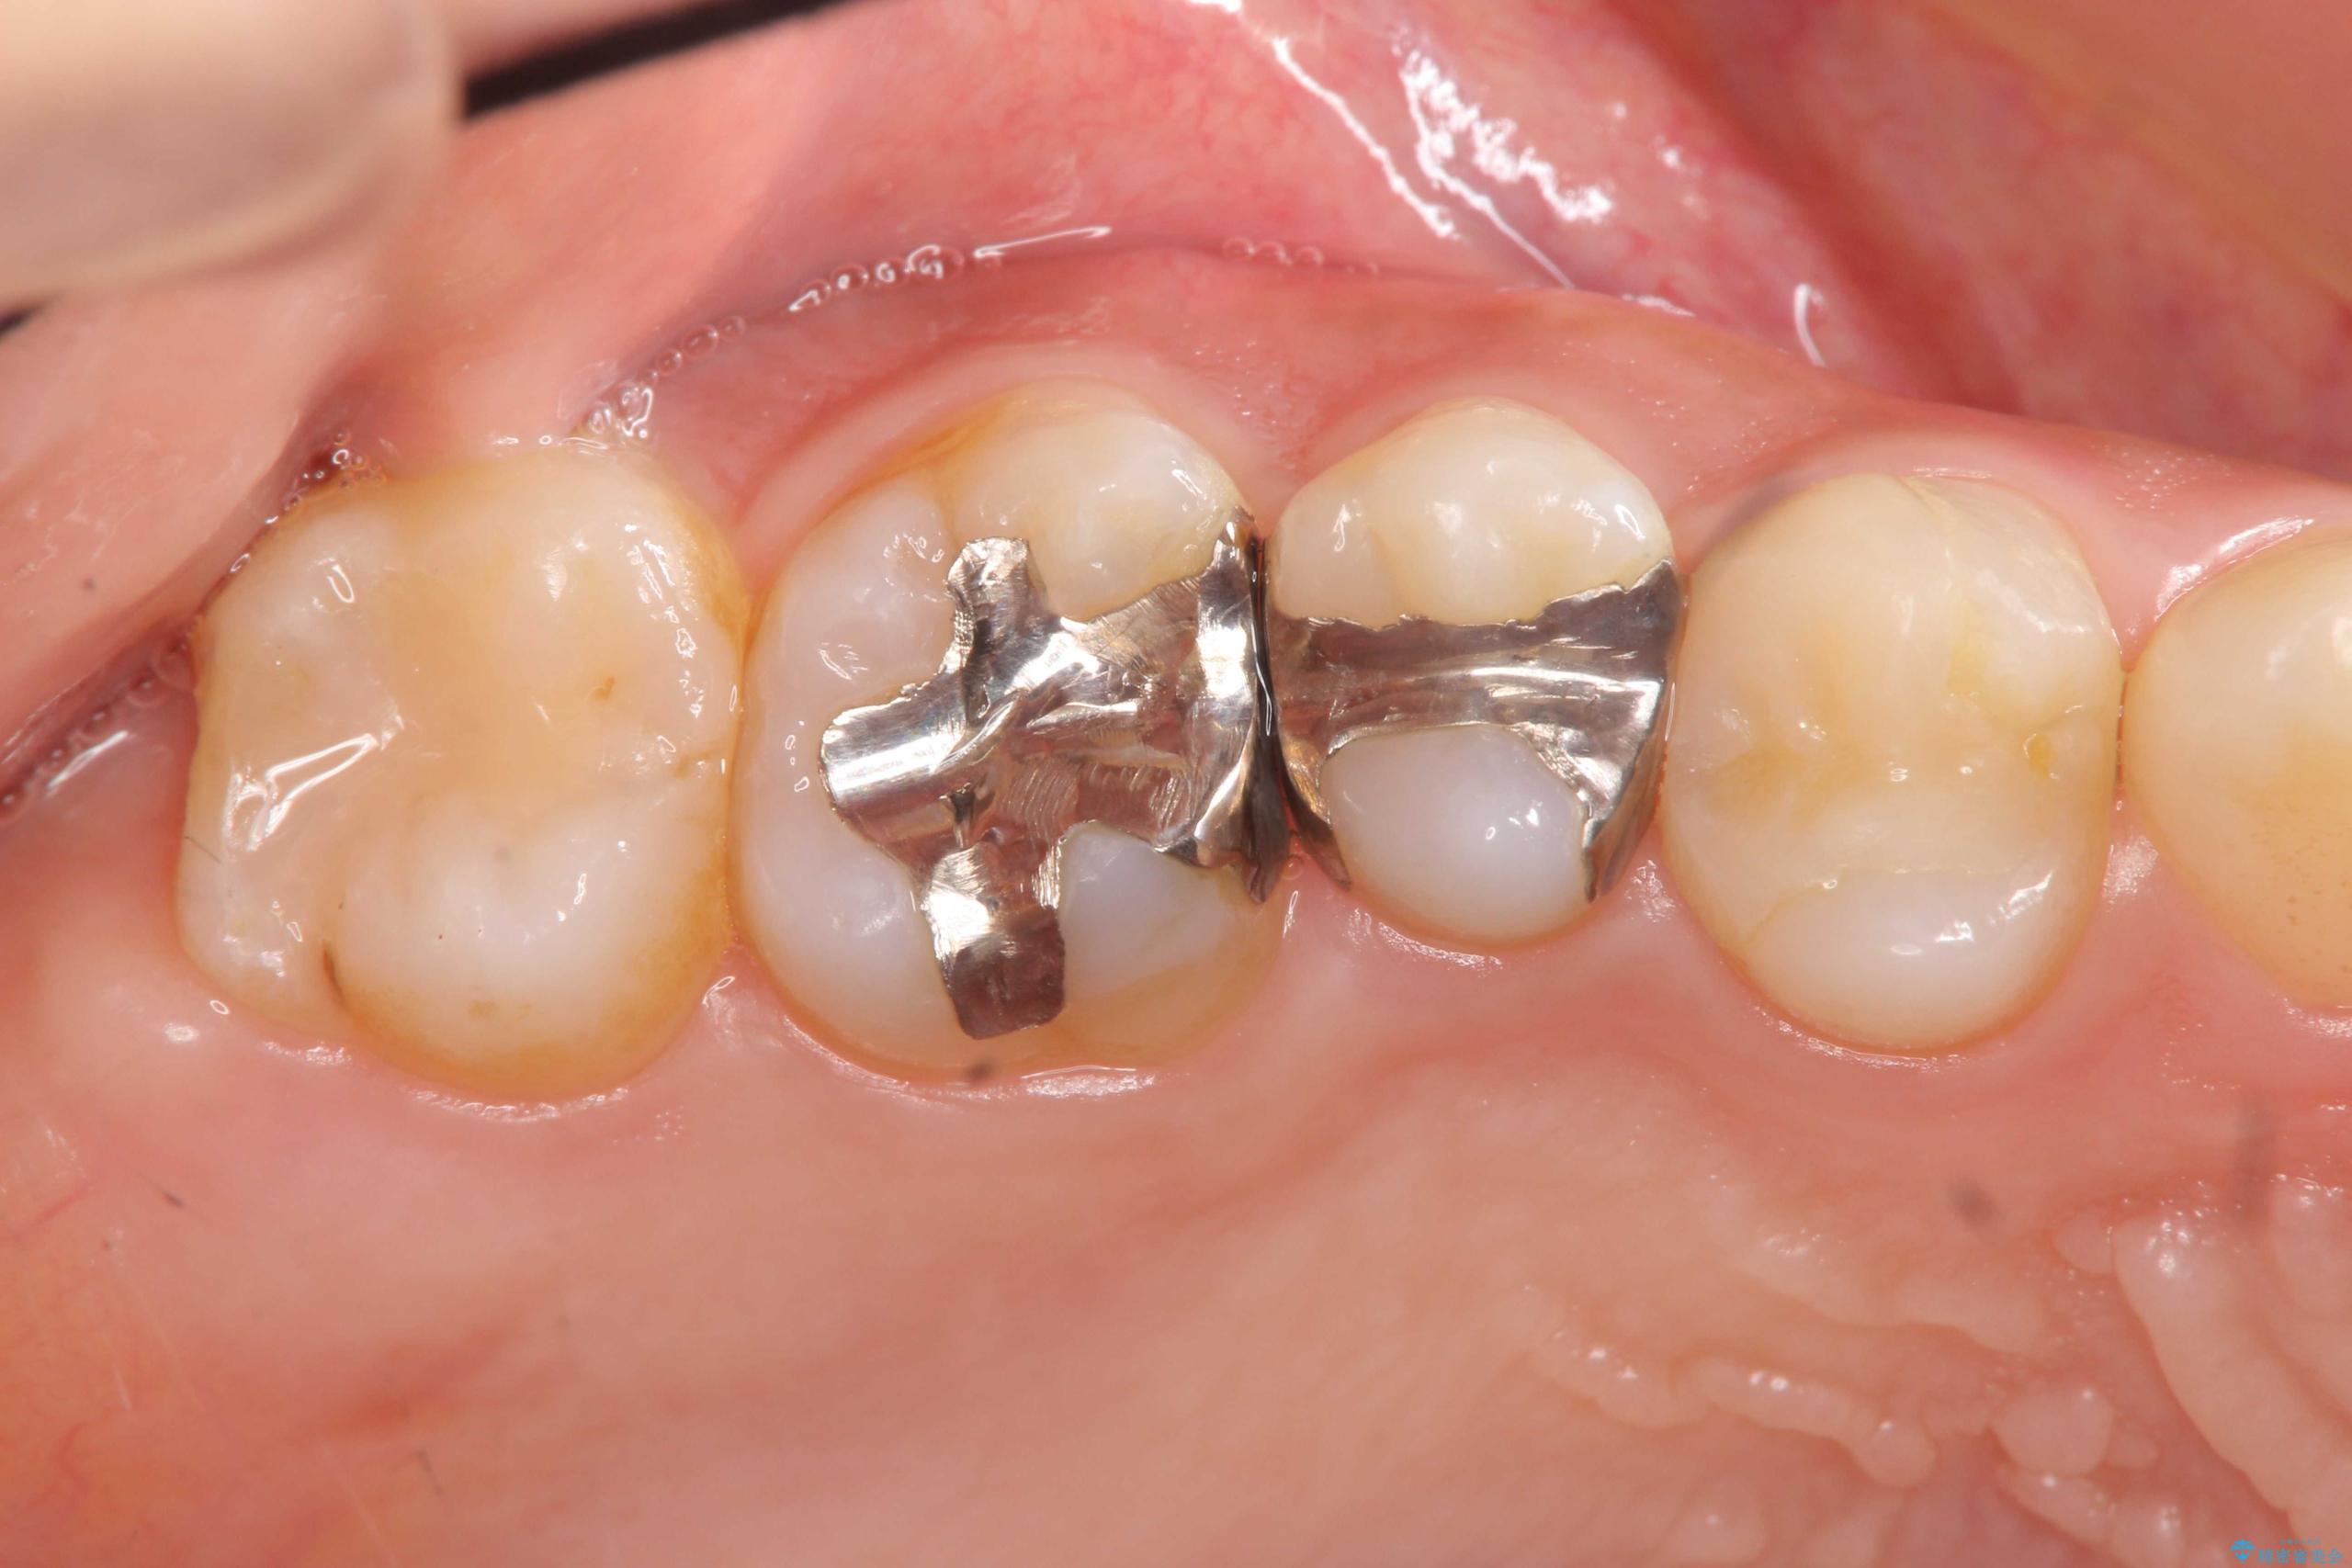

治療前

銀歯を除去してのセラミック治療[ メタルフリー ] 治療前画像 銀歯を除去してのセラミック治療[ メタルフリー ] 治療前画像 銀歯を除去してのセラミック治療[ メタルフリー ] 治療前画像